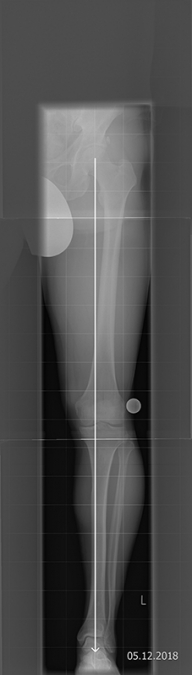

UMSTELLUNGSOSTEOTOMIE

Eine Möglichkeit der Behandlung von Verschleißleiden ist die Umstellungsosteotomie. Nach Unfällen aber auch angeboren können erhebliche Achsenabweichungen an den Beinen vorliegen. Solche Abweichungen von der zentralen Tragachse führen zu schmerzhaften Fehlbelastungen und einem vorzeitigen Verschleiß des überlasteten Gelenkabschnittes. Die Korrektur solcher Achsenabweichungen führt zu einer gleichmäßigeren Belastung des Kniegelenkes und dann auch zum Rückgang der Beschwerden.  Man unterscheidet verschiedene Techniken der Osteotomien, wie schließende und öffnende Osteotomien, die je nach Fehlstellung und vorliegendem Verschleißbild angewendet werden können.

Wir führen Umstellungsosteotomien nach Analyse computerunterstützt durch. Hierdurch kann eine hohe Genauigkeit bei der Durchführung erzielt werden.

Nach solchen Operationen ist in den meisten Fällen eine Teilbelastung notwendig, um die Knochenheilung zu schützen. Der Prozess der „Umgewöhnung“ des Gelenkes nimmt eine Zeit von ca. 3 -6 Monaten in Anspruch. Es kann durch solche Korrekturen in vielen Fällen ein künstliches Gelenk über 10 Jahre und mehr vermieden werden.

Bild HTO mit Tomofixplatte vor OP